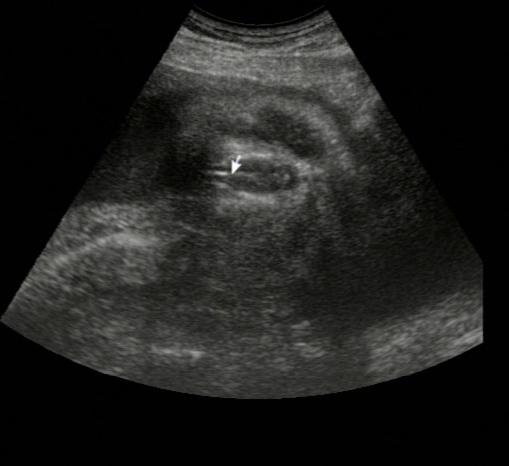

akkor jönnek képek:

Mikor még fiú volt, és hozzá az akkori magyarázat: Kép

Itt pedig már lány: Kép

Kép magyarázat: jobbra a nagy kör a feje, bal oldalon alul és felül van egy-egy fehér csík az a csont a lábában és a két csont között volt akkor a lényeg amit a doki azzal a vonnallal jelölt meg, a kisebbik kék körre a fütyit mondta a nagyobbikra a zacsit! Én akkor ezt így el is tudtam képzelni, ma már nem tudom akkor mi volt ott :lol: :lol: Nekem a második képen is az bármi lehet, a doki szerint punci!! Én már tényleg csak azt fogom elhinni amit a kezmben tartok majd!! :?